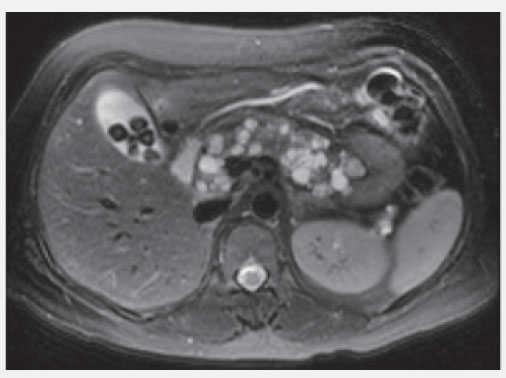

Estudios de imagen:Figura 1. Quistes pancreáticos.

Figura 3. IRM quistes pancreáticos.